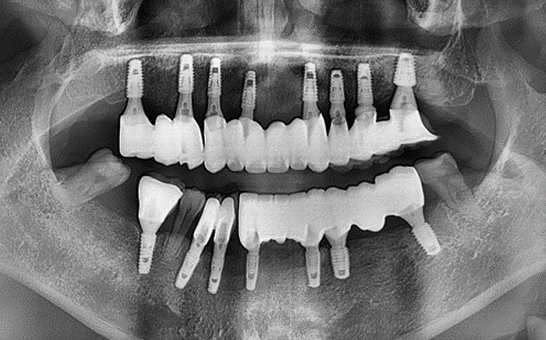

CASE 01 김** / 60대

전악임플란트

치료 시작 전 촬영 2024.01.24 | 치료 완료 후 촬영 2024.12.26

1 예후불량 치아 발치

2 발치 후 즉시 임플란트 식립 및 뼈이식

3 고정성 보철물로 수복 후 일상 회복